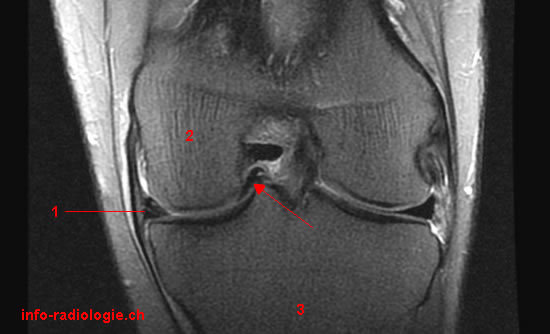

IRM du genou pour douleurs et hydarthrose récidivante: que voit-on?

Anse de seau du ménisque

Un patient s’est présenté aux urgence pour blocage aigu du genou, une IRM est réalisée que voit-on?

Anse de seau luxée dans l’échancrure intercondylienne